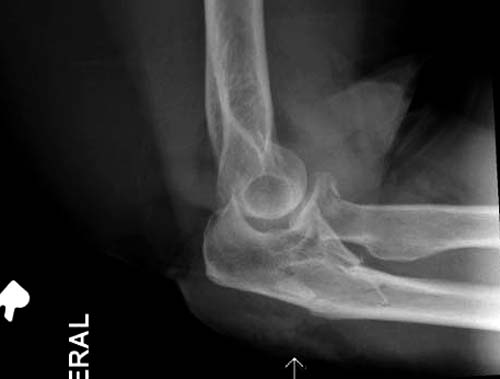

Один снимок всего? Может КТ-срезы какие-нибудь есть, R-снимки без гипса фас/профиль? По этому снимку вроде бы и нет вдавленного перелома. Суставная поверхность расколота - это да, но импрессии не увидел. Мы бы попытались сохранить головку.

На представленных снимках есть смещение суставной поверхности. Принцип лечения внутрисуставных переломов - восстановление суставной поверхности. У нас есть опыт восстановления таких переломов микровинтами. Удачи!

Вместе обычных простых рентгенограм, участились злоупотребления дорогими исследованиями. Хотя многие переломы, даже внутрисуставные, можно увидеть на обычных рентген снимках. Негативный рентген при исследовании локтевого сустава не означает отсутствие перелома. Если имеется “fat pad sign”, характерный симптом для внутрисуставных повреждений, тогда можно ставить диагноз перелом головки луча! Гематома внутрисуставного перелома смещает жировое тело и на боковом снимке проявляется в виде “паруса”.

На переломы головки луча надо обратить внимание, потому что головка луча является важным стабилизатором в локтевом суставе: удерживает от заднего вывиха и от боковых смещений. Изолированный перелом головки луча встречается очень редко и, в основном, в сопровождении с другими повреждениями, вывихом сустава, переломом Monteggia, венечного отростка или повреждением латерального лигамента.

Для выработки показаний достаточным бывают стандартные снимки, но иногда требуется косая рентгенограмма по Coyle. И для подтверждения смещений и оценки внутрисуставных фрагментов рекомендуется КТ, а 3D снимки показывают только поверхность, т.е. получается общая картина. МРТ дает возможность оценить состоянии связок.

Переломы по Mason первой степени без блокировки и смещение до 2х мм можно лечить в обычной косынке, или брейсом - консервативно. Перелом второй степени оперативно, а многооскольчатые переломы третьей степени лечатся заменой головки.

В первом случае перелом Монтеджи, где доперационно сделано оценка положения головки к остальным элементам под рентгеном. Учитывая правильность взаимотношении произведена фиксация только локтевого отростка, Второй случай, заменена на протез, и третий, кроме фиксации головки - реконструкция capitellum латерального мыщелка.